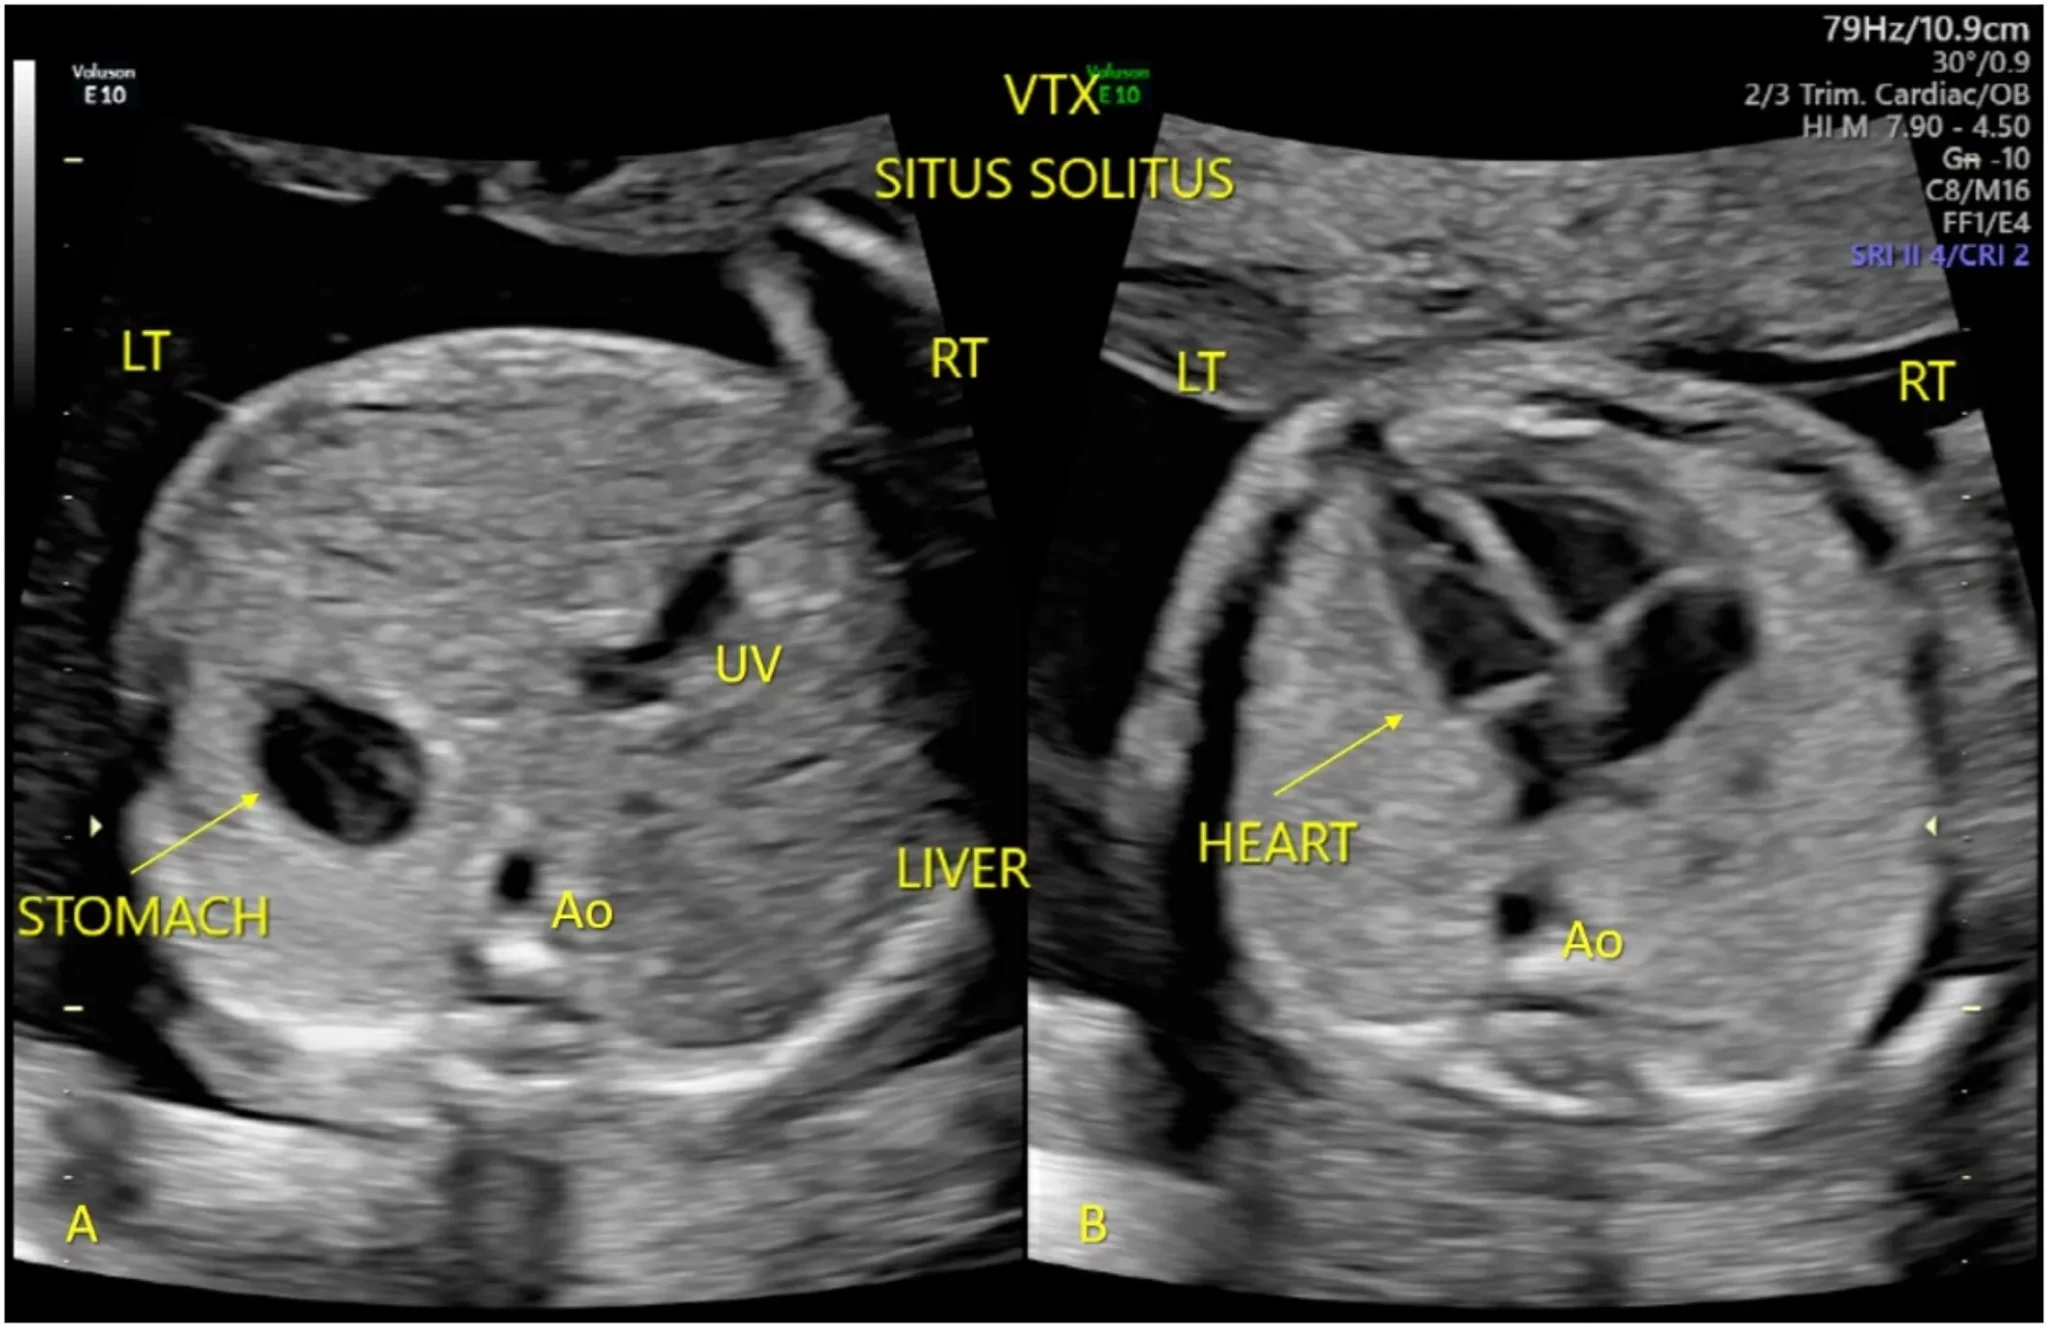

3. Fetal Cardiac Screening: What Every Radiologist Must Know with Dr. Ekta Mishra

Prenatal radiology is incomplete without fetal heart screening. This session takes you from basics to expert-level protocols.

• Key views & markers in fetal echocardiography

• Structural & rhythm abnormalities

• When to refer and what to flag early